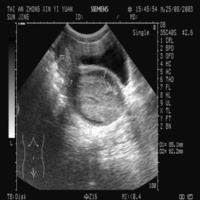

處女膜形態隨著雌性的漸漸成長,成年處女膜的形態開始變得千差萬別,甚至有的個體先天沒有處女膜,當然有些動物沒有處女膜的原因是因為處女膜在胚胎期就消失了,但這樣的動物往往性成熟早。這層膜的常見類型主要如圖:在這眾多類型中,比較極端的是處女膜閉鎖(Imperforate hymen),其次為處女膜開口過小(Microperforate hymen)。在沒有及時發現的情況下,它會阻擋經血流出,導致陰道積血(haematocolpos)並造成腹痛。最常用的治療方法為處女膜切開術:用一個“T形”,“X形”,或者“十形”的切口打開處女膜,並移去多餘的組織。

石女透視圖所謂“石女”常常是指處女膜閉鎖,陰道橫膈,先天性無陰道或陰道閉鎖。這種先天性缺陷並非一生下來就能引起人們的注意,有的人是到了青春發育期還遲遲不來月經,另有些人甚至是到了洞房之夜不能性交才被發現。正常女性,在尿道口的下方有一個陰道口,在陰道口周圍有一層薄膜組織叫處女膜,一般正常的情況處女膜只有一個孔,月經血從此流出。如果處女膜上有許多小孔便成為篩狀處女膜,如果沒有就成為處女膜閉鎖了。如子宮陰道發育不正常,初潮後就會因經血不能排出而積存於陰道子宮積血;積血過多還可通過輸卵管進入腹腔,輸卵管傘部附近的腹膜受月經血刺激發生水腫,粘連,會使傘部閉鎖,形成陰道-子宮-輸卵管積血。這種人常在青春期後遲遲不來月經,但卻有每月一次的肚子疼,並且疼痛一次比一次加重。如果結了婚也不能同房。這種情況應該早就醫,及時確診。其治療是很簡單的,只要切開處女膜,放出積血,問題也就解決了。一般不影響結婚及生育。